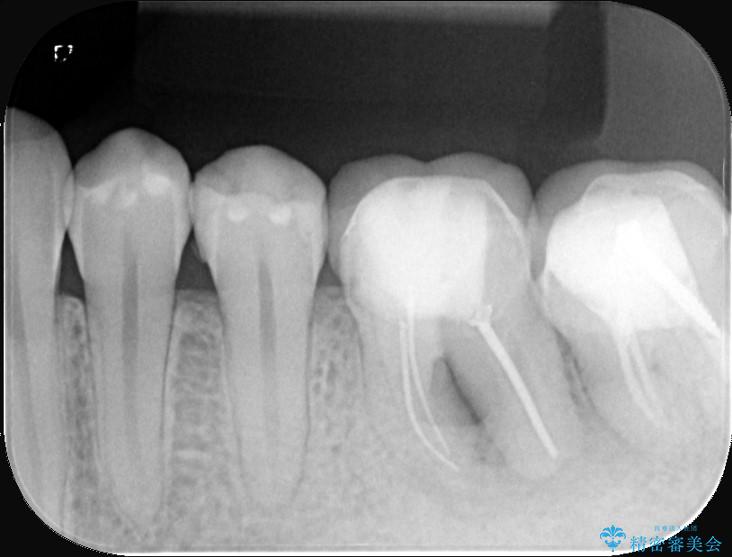

保存が難しい左下6番目の歯を抜歯し、左下8番目の歯(親知らず)を抜歯窩に移植しました。歯牙移植後の動揺防止のため暫間固定を行っています。

また移植後2週間経過時点で根管処置が必要となります。

骨との定着を確認し、今後矯正治療を行う予定のためレジン冠をセットしています。